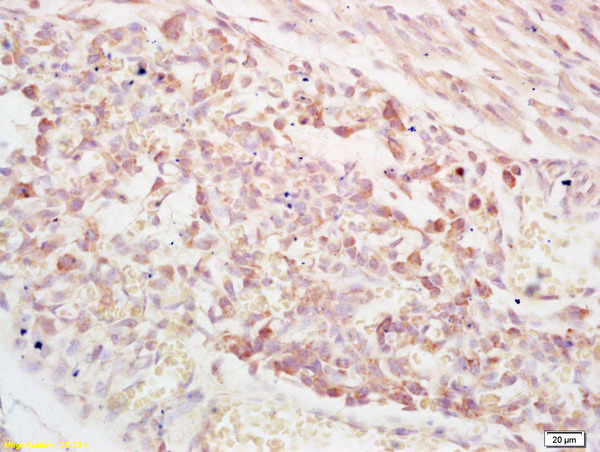

ApplicationsImmunoFluorescence, ELISA, ImmunoHistoChemistry, ImmunoHistoChemistry Frozen, ImmunoHistoChemistry Paraffin

- Applications SupplierELISA(ELISA=1:30-3000), IHC-P(IHC-P=1:100-1:200), IHC-F(IHC-F=1:100-1:200), IF(IF=1:100-1:200)